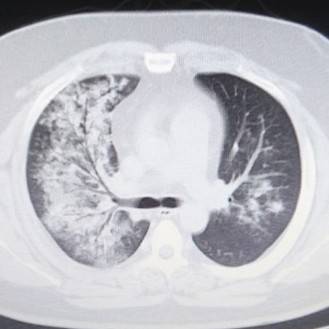

CTの写真を何枚か見てみましょう。

これならわかる。

CTは肺炎を見つけるのが得意です。

イガイガと汚く見えるところが肺炎です。

撮影した時点では肺炎かどうかはわからないので、放射線科内でも「ココが汚い」という表現をよくします。

もう一度、先程のCTを見てみると汚い部分がくっきりと限局しているのがわかります。

このような肺炎を区域性肺炎といいます。

肺がんの場合は浸潤していくので肺の区域に関係なく大きくなっていきます。